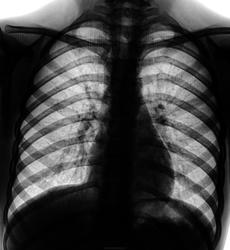

Снимок "дитяти" и только в прямой проекции.

Что посоветуете в протоколе написать Уважаемые Коллеги?

Я за норму, но я от детей далека.

Корни не нравятся...

Только кашель, ну а на вид "дохловат" мал-мал....

На томках легочных очагов нет. К чему можно придратся - в левом корне лимфоузлы уплотненные (или даже кальцинированные).

Я по "ребенкам" не очень. Может перенес туберкульоз внутригрудных л/у. Возможно реактивация пошла, раз он худой на вид. Других мыслей нет.

Ну и зачем ЛТ, если по ней нельзя вынести заключение??? Томографировать детей - мягко говоря, это неправильно. Что режем, зачем? Без бокового? Кошмар. Боковой делаем, ставим первичный туб.комплекс в S6 (к примеру) под вопросом и на консультацию к фтизиатру. А там уж решается: просто инфильтрация, не просто, какие контроли и дообследования.